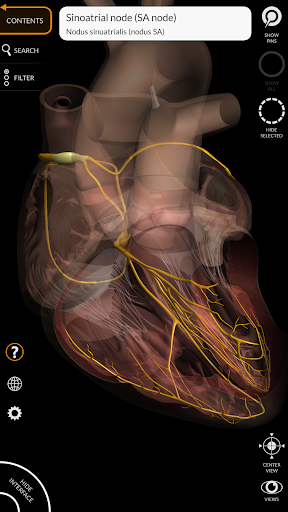

"Anatomía - Atlas 3D" permite estudiar la anatomía humana de forma fácil e interactiva.

A través de una interfaz sencilla e intuitiva es posible observar cada estructura anatómica desde cualquier ángulo.

Los modelos anatómicos 3D son especialmente detallados y con texturas de hasta una resolución de 4k.

MODELOS ANATÓMICOS 3D

• Sistema cardiovascular • Sistema